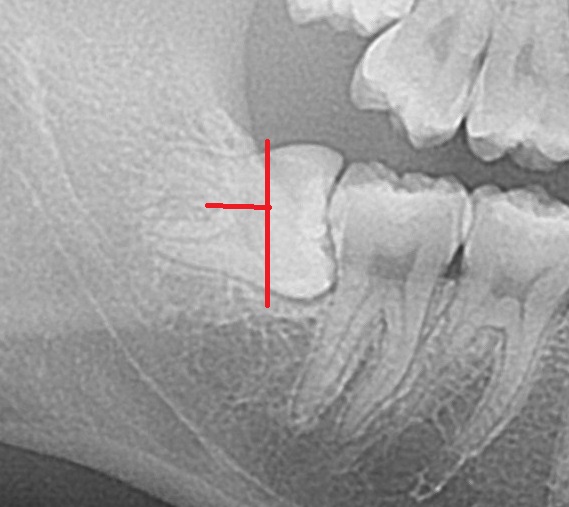

右下の親知らずで、横向きに生えています。

水平埋伏智歯と呼ばれる歯です。

横向きの親知らずは、歯を分割して取り出します。

赤線のように歯を切って、取り出します。

矢印の方向に根の先が90度曲がっています。

顎の骨の中で引っかかるので、根が曲がった歯(弯曲根)は

治療の難易度が高くなります。